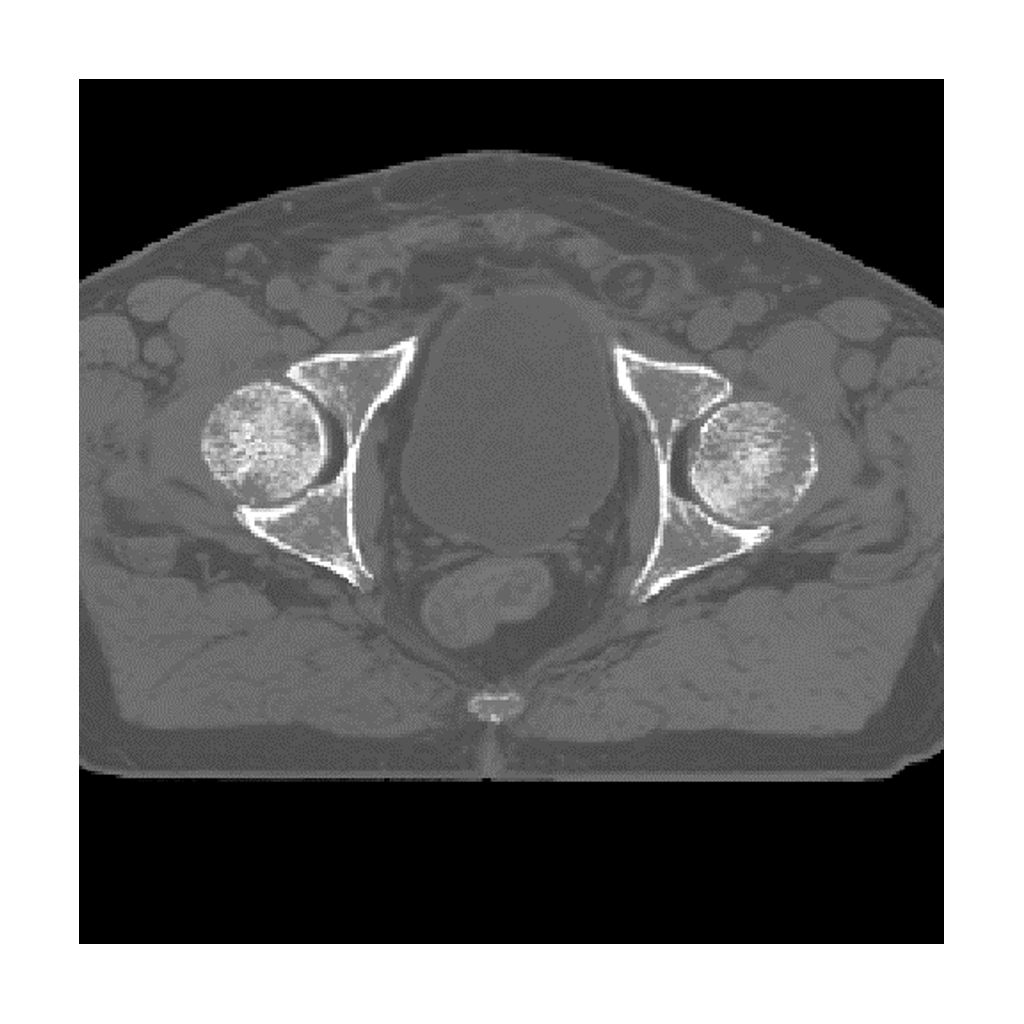

MRCAT Pelvis

MRCAT Pelvis is intended for radiotherapy planning of primary and metastatic tumors in the pelvis. MRCAT Pelvis is empowered by Compressed-SENSE which results in a scan time below 3.5 minutes, with a large FOV of up to 360mm in feet-head direction.

Onesite web image MRCAT pelvis